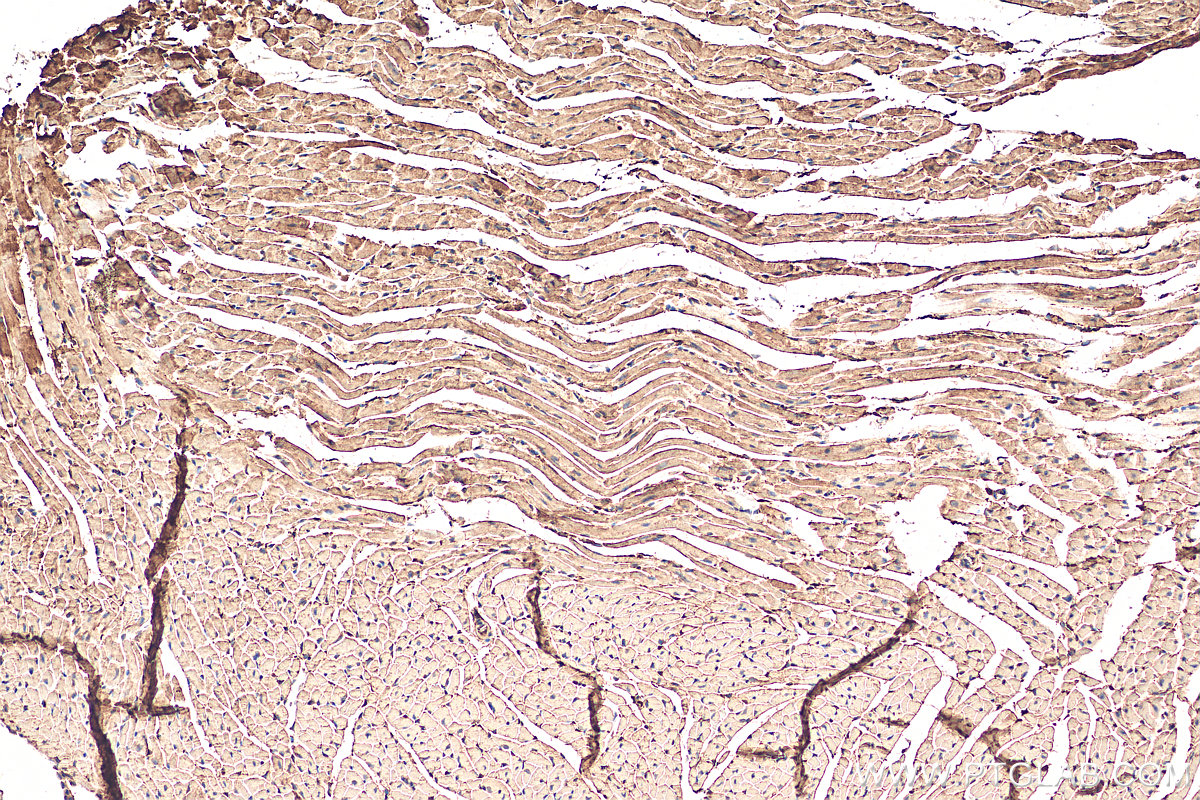

| Positive IHC detected in | mouse heart tissue, human lung cancer tissue, human heart tissue, human spleen tissue Note: suggested antigen retrieval with TE buffer pH 9.0; (*) Alternatively, antigen retrieval may be performed with citrate buffer pH 6.0 |